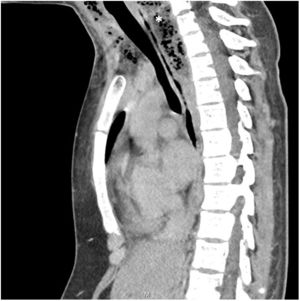

Paciente mujer de 17 años con antecedentes de meningoencefalitis en la infancia sin secuelas, que consultó por un cuadro clínico de una semana de evolución consistente en dolor cervical, odinofagia y fiebre de hasta 39°C. En la exploración física las constantes fueron estables, presentando dolor cervical a la movilización. En la analítica presentó elevación de reactantes de fase aguda. Se realizó una TAC cervical y torácica en la que se observó una gran colección cervical con abundantes burbujas de gas en su interior (figs. 1-3, asteriscos), con extensión hacia el mediastino posterior a través del espacio peligroso retrofaríngeo, hallazgos compatibles con fascitis necrosante y mediastinitis posterior. En las muestras quirúrgicas se cultivó Streptococcus dysgalactiae y S. intermedius. La paciente evolucionó favorablemente con tratamiento antibiótico y drenaje quirúrgico de la colección.